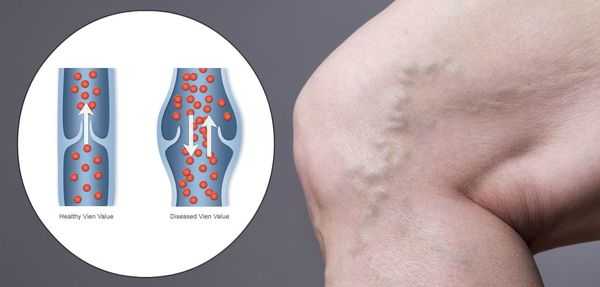

Под воздействие силы тяжести кровь в сосудах спускается в нижние конечности, организму приходится прилагать усилия для ее подъема. Препятствуют оттоку крови вниз венозные клапаны, которым активно помогает в этом физическая активность, сокращение мышц и сгибание колен. Совокупность этих факторов обеспечивает нормальный кровоток.

Поддержание постоянного сопротивления силы тяжести возможно из-за физиологического изменения просвета сосудов при смене положения тела, работе клапанного аппарата и тонусу (эластичности) венозной стенки. Если один из этих составляющих механизмов нарушается, патологические процессы начинают затрагивать всю систему в целом. Потеря эластичности участка вены ниже клапана, и ее расширение приводит к клапанной несостоятельности, невозможности удерживать кровоток для последующего подъема. Застой жидкости приводит к повышению давления для продвижения крови вверх. Но, с течением времени повышенное давление увеличивает объем части вены, потерявшей эластичность.

К патологическому процессу может присоединиться венозный рефлюкс (обратный ток крови сверху вниз). Жидкость начинает застаиваться, давить на стенки сосуда. В результате плазма крови просачивается в окружающие ткани, вызывая отек. Аналогично ситуация развивается при изначальной клапанной недостаточности.